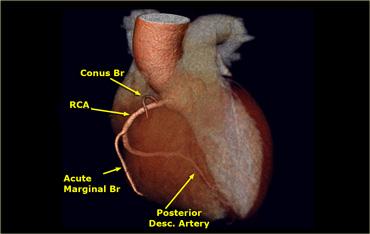

Động mạch vành phải (RCA)

Động mạch vành phải xuất phát từ xoang Valsalva trước và đi qua rãnh nhĩ thất phải (AV) giữa nhĩ phải và thất phải đến phần dưới của vách liên thất.

Trong 50-60% trường hợp, nhánh đầu tiên của RCA là nhánh nón nhỏ, cấp máu cho đường ra thất phải.

Trong 20-30% trường hợp, nhánh nón xuất phát trực tiếp từ động mạch chủ.

Trong 60% trường hợp, động mạch nút xoang xuất phát như là nhánh thứ hai của RCA, chạy ra sau đến nút xoang nhĩ (trong 40% trường hợp nó xuất phát từ Cx).

Các nhánh tiếp theo là một số nhánh chéo chạy ra trước để cấp máu cho thành trước của thất phải.

Nhánh bờ cấp lớn (AM) tách ra với góc nhọn và chạy dọc theo bờ của thất phải phía trên cơ hoành.

RCA tiếp tục đi trong rãnh nhĩ thất ra phía sau và cho một nhánh đến nút nhĩ thất.

Trong 65% trường hợp, động mạch liên thất sau (PDA) là một nhánh của RCA (tuần hoàn ưu thế phải).

PDA cấp máu cho thành dưới của thất trái và phần dưới của vách liên thất.

Nhánh bờ cấp lớn (AM) cấp máu cho thành bên của thất phải.

Trong trường hợp này có tuần hoàn ưu thế phải, vì động mạch liên thất sau (PDA) xuất phát từ RCA.